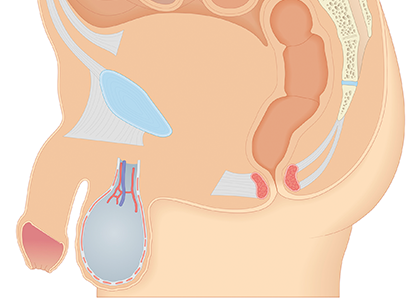

고환은 정자와 테스토스테론을 생성하는 중요 기관입니다. 고환/부고환염, 고환염전, 정계정맥류, 음낭수종 등 고환에 발생할 수 있는 다양한 질환을 적절한 방법으로 치료해야 합니다.

고환이나 부고환의 외상이나 요도로부터 소변이 역류가 되어 발생하기도 하지만 대부분의 경우 요로 감염에 의해 발생하게 됩니다. 세균이 요도나 전립선에 존재하다가 소변의 압력에 의해 고환이나 부고환에 도달하게 되어 염증을 일으키게 됩니다.

심한 통증이 갑자이 음낭 내에서 발생하게 되고 심할 경우 하복부 통증이 동반되기도 합니다.

고환으로 들어가는 정삭의 꼬임으로 고환으로 혈액 공급이 차단되어 고환의 통증을 유발하는 질환으로 주로 사춘기 남아에게서 많이 발생합니다.

사춘기에 고환의 성장이 진행되면서 정삭을 둘러싸고 있는 근육의 수축으로 발생할 수 있으며 극심한 고환통과 구역질, 구토가 동반될 수 있습니다.

음낭 내에 있는 정맥의 혈관이 확장되어 음낭에 울퉁불퉁한 모습으로 확장된 혈관이 관찰되는 질환입니다.

배변을 할 때 아랫배에 힘을 주게 되면 겨우 만져지는 경미한 정계정맥류가 있을 수 있고, 심할 경우 음낭에 벌레가 기어다니는 듯한 확장된 혈관이 관찰될 수 있습니다.

고환 주위에 물이 차는 지로한으로 고환을 둘러싸고 있는 초막에 액체가 고이는 질환입니다. 액체가 점차 부풀어오르기 때문에 방치하면 커다란 종물로 만져질 수 있습니다.

소아의 경우 고환을 둘러싸고 있는 초막이 복강과 연결되어 있어서 복강 내 복수가 음낭내로 내려와 발생할 수 있으며, 성인의 경우 초막 내에 정상적으로 존재하는 고환수에 대한 분비과 흡수 사이의 불균형에 의해 발생합니다.